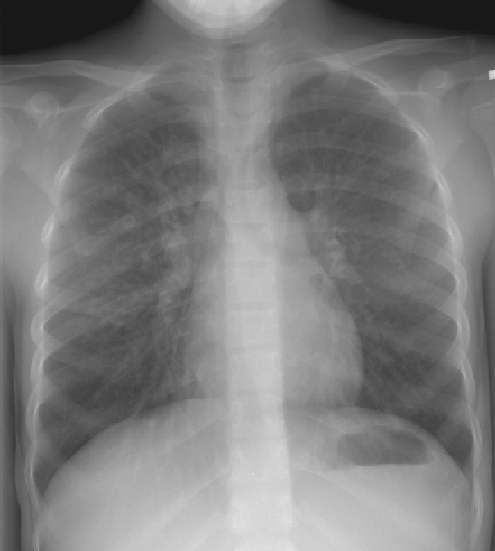

The patient below was an 8 year old boy who had repeated episodes

of sinusitis and recurrent upper respiratory infections. The chest

radiograph demonstrates both cardiac and abdominal situs inversus.

There is a left lingular infiltrate (best seen on the lateral

view). A sinus CT on this patients demonstrates evidence of pansinusitis

(Click here to view sinus CT).